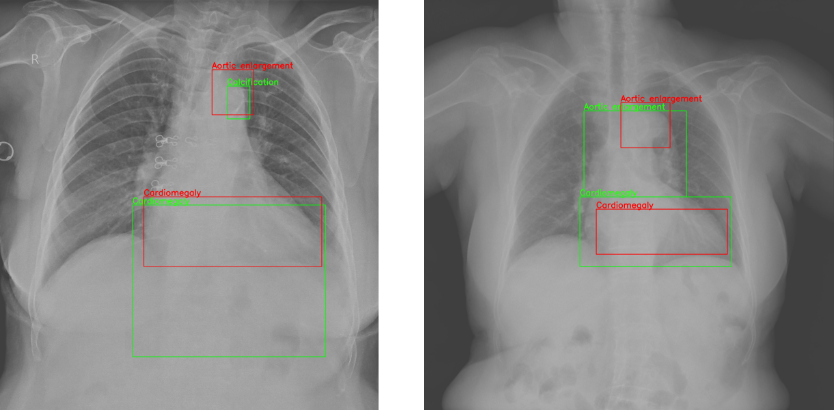

Figure 3: The visualization of bounding boxes is shown in Table 7. The red rectangles indicate the model’s predicted boxes, while the green rectangles indicate the ground truth boxes. In the image on the left side, representing example 1, the red box at the top represents Aortic enlargement, the green box at the top represents Calcification, and the boxes at the bottom represent Cardiomegaly. In the image on the right side, representing example 2, the red and green boxes at the top represent Aortic enlargement, and the boxes at the bottom represent Cardiomegaly.

In this section, we present quantitative results to demonstrate the effectiveness of our method. The generated results are illustrated in Table 7, and the visualization of the bounding boxes is shown in Figure 3.

As illustrated in Example 1, we could easily observe that Cardiomegaly is detected correctly, and the predicted region closely matches the ground truth. Additionally, while the model incorrectly classified Calcification and Aortic Enlargement, the predicted bounding box aligns with the ground truth. As shown in Example 2, the results are more accurate, with both Aortic Enlargement and Cardiomegaly correctly classified, and the regions indicated by these detections are acceptable. Overall, diagnosing and detecting anomolies in medical images is challenging not only for radiologists but also for advanced artificial intelligence systems due to variability in diagnoses resulting from different perspectives of radiologists. These models should serve as assistants, providing additional information and recommendations to support radiologists in making decisions.